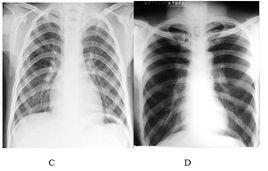

醫學攝影學本專業培養具有基礎醫學、臨床醫學和現代醫學影像學的基本理論知識及能力,能在醫療衛生單位從事醫學影像診斷、介入放射學和醫學成像技術等方面工作的醫學高級專門人才。 業務培養要求:本專業學生主要學習基礎醫學、臨床醫學、醫學影像學的基本理論知識,受到常規放射學、CT、磁共振、超聲學、DSA、核醫學影像學等操作技能的基本訓練,具有常見病的影像診斷和介入放射學操作基本能力。 畢業生應獲得以下幾方面的知識和能力:1.掌握基礎醫學、臨床醫學、電子學的基本理論、基本知識;2.掌握醫學影像學範疇內各項技術(包括常規放射學、CT、核磁共振、DSA、超聲學、核醫學、影像學等)及計算機的基本理論和操作技能;3.具有運用各種影像診斷技術進行疾病診斷的能力;4.熟悉有關放射防護的方針,政策和方法,熟悉相關的醫學倫理學;5.了解醫學影像學各專業分支的理論前沿和發展動態;6.掌握文獻檢索、資料查詢、計算機套用的基本方法,具有一定的科學研究和實際工作能力。 主幹課程:主幹學科:基礎醫學、臨床醫學、醫學影像學。主要課程:物理學、電子學基礎、計算機原理與接口、影像設備結構與維修、醫學成像技術、攝影學、人體解剖學、診斷學、內科學、影像診斷學、介入放射學。 修業年限:五年授予學位:醫學學士相近專業:臨床醫學麻醉學醫學影像學醫學檢驗放射醫學視光學康復治療學精神醫學醫學技術聽力學醫學實驗學臨床醫學醫療美容技術醫學影像技術康復治療技術醫學檢驗技術